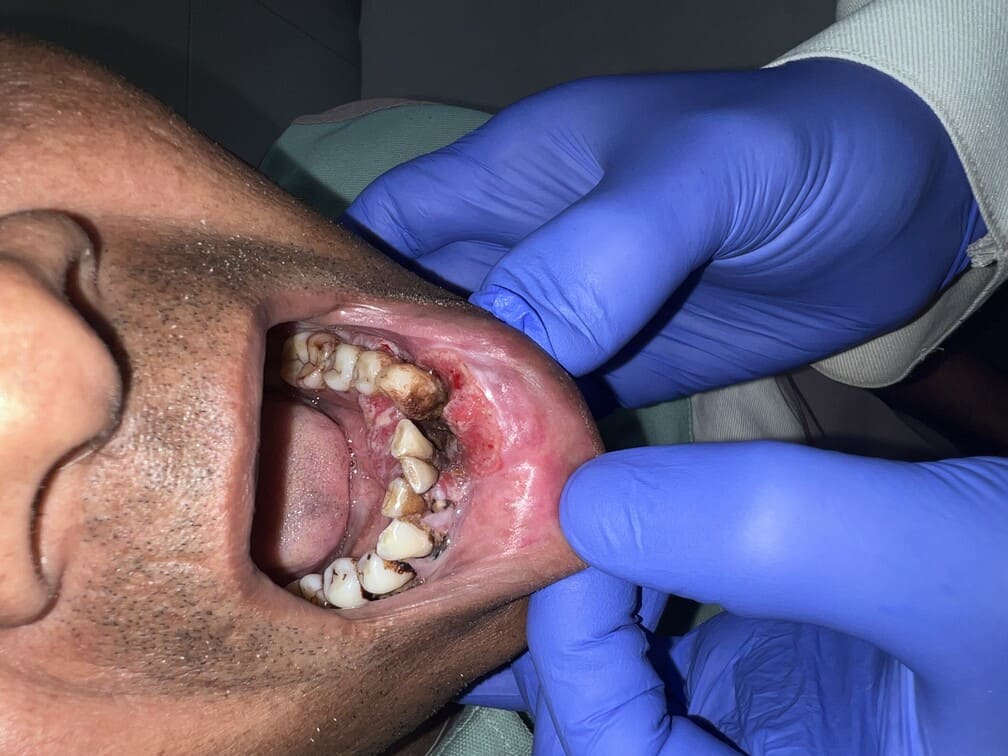

57 years old female suffering from left buccal mucosa growth involving left RNT and gingival surface of lip extending up to right angle mouth.left modified neck dissection with left distal segmental mandibulectomy with wide excision of left buccal mucosa with left RMT growth with excision gingival margin of lower lip with left pectoralis with right nasolabial flape done.

29-12-2025